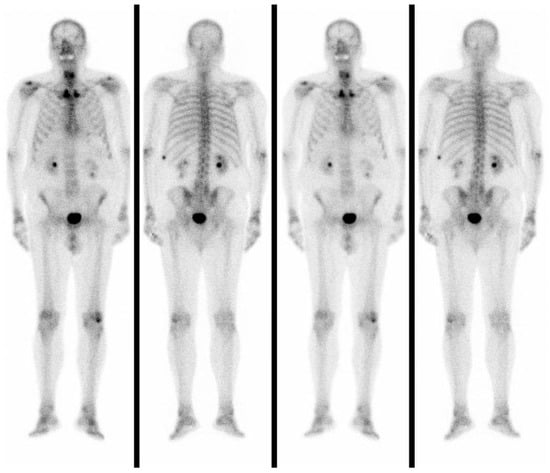

In a total-body bone scintigraphy, the accumulation of 99mTc was not detected in the anterior neck but only in the left X rib, which was the site of a previous fracture (Figure 4).

Negative total-body bone scintigraphy and the absence of disseminated disease misled us to misdiagnosis because we knew, from the literature, that unusual skeletal metastases of gastrointestinal adenocarcinoma occur more frequently in the case of liver and/or lung involvement than in patients without a disseminated disease [14,18]. In summary, osteolysis of the hyoid bone should be suspected of metastases in patients with a history of rectum and sigmoid colon adenocarcinoma.

Figure 4. Total-body bone scintigraphy showing the accumulation of 99 mTc that was not detected in the anterior neck but only in the left X rib which was the site of a previous fracture.